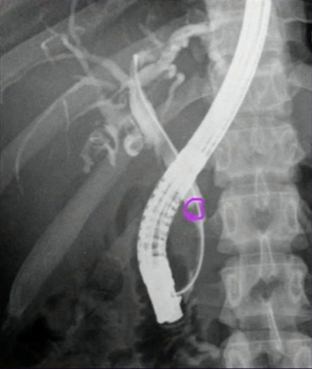

Q

Quem sou eu?

A

CPRE

How well did you know this?